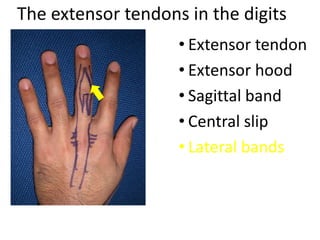

- It describes flexor tendon zones, extensor compartments, and pulley system anatomy.